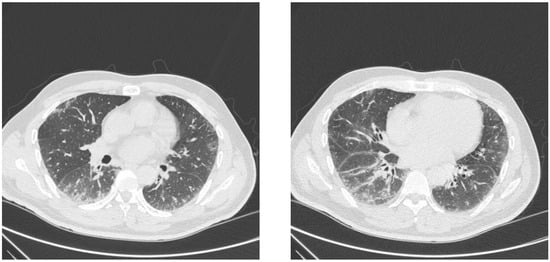

7. Imaging and Histology

- Waseda, Y.; Johkoh, T.; Egashira, R.; Sumikawa, H.; Saeki, K.; Watanabe, S.; Matsunuma, R.; Takato, H.; Ichikawa, Y.; Hamaguchi, Y.; et al. Antisynthetase syndrome: Pulmonary computed tomography findings of adult patients with antibodies to aminoacyl-tRNA synthetases. Eur. J. Radiol. 2016, 85, 1421–1426. [Google Scholar] [CrossRef]

- Debray, M.P.; Borie, R.; Revel, M.P.; Naccache, J.M.; Khalil, A.; Toper, C.; Israel-Biet, D.; Estellat, C.; Brillet, P.Y. Interstitial lung disease in anti-synthetase syndrome: Initial and follow-up CT findings. Eur. J. Radiol. 2015, 84, 516–523. [Google Scholar] [CrossRef]

- Yamakawa, H.; Hagiwara, E.; Kitamura, H.; Iwasawa, T.; Otoshi, R.; Aiko, N.; Katano, T.; Shintani, R.; Ikeda, S.; Okuda, R.; et al. Predictive Factors for the Long-Term Deterioration of Pulmonary Function in Interstitial Lung Disease Associated with Anti-Aminoacyl-tRNA Synthetase Antibodies. Respiration 2018, 96, 210–221. [Google Scholar] [CrossRef]